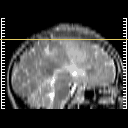

Click on sagittal image to select slice. Click on thin tickmark to change timepoint, or thick tickmark for overlay.